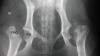

VÍDEO: Necrosis aséptica de la cabeza y cuello femoral